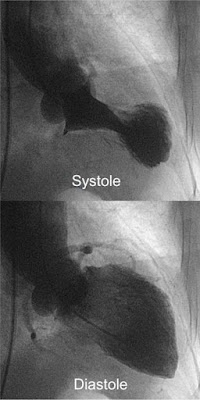

Рисунок 6а: Изменения ЭКГ при кардиомиопатии Такоцубо — адаптировано из Namgung в Clin Med Insights Cardiol (см. текст).

Рисунок 6б: Данные вентрикулографии при КМ Такоцубо (взяты из той же статьи) хорошо иллюстрируют баллонирование.